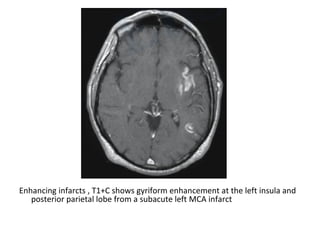

Enhancing infarcts , T1+C shows gyriform enhancement at the left insula and

posterior parietal lobe from a subacute left MCA infarct

Enhancing infarcts , T1+C shows gyriform enhancement at the

left insula and posterior parietal lobe from a subacute left

MCA infarct